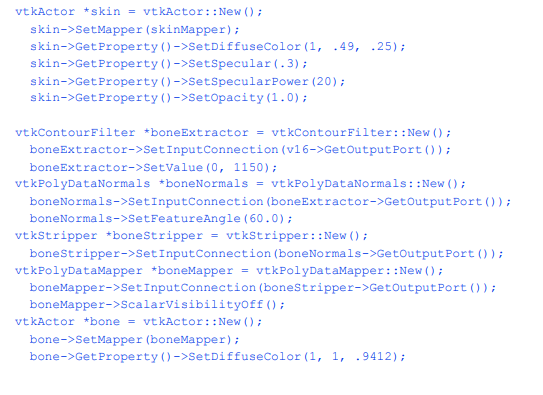

我们将提取三个正交平面,对应于放射科医生熟悉的轴向、矢状和冠状截面。轴向面垂直于患者颈部,矢状面从左到右,冠状面从前到后。为了便于说明,我们使用不同颜色的查找表来呈现每个平面。对于矢状面,我们使用灰度。冠状面和轴向面分别改变饱和度和色相表。我们将其与皮肤的半透明渲染相结合(我们使用c++语句bone- >VisibilityOff()关闭骨骼)。下面的VTK代码创建了纹理映射过程中使用的三个查找表。